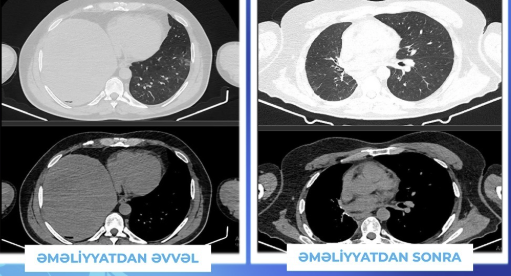

Bildirilib ki, aparılan müayinələr zamanı sağ döş qəfəsi boşluğunun böyük hissəsini dolduran, ətraf orqanlarla yaxın təmasda olan, təxmini ölçüsü 18 sm olan, nəhəng və solid ağciyər törəməsi aşkarlanıb.

Sağ ağciyərin orta və aşağı pay lobektomiyası ilə birlikdə, diafraqma rezeksiyası və rekonstruksiyası da icra edilərək invaziv törəmə en bloc şəkildə çıxarılıb.

Patologiya nəticəsində, çıxarılmış törəmənin ağciyərdə son dərəcə nadir rast gəlinən Solitar Fibroz Tümor olduğu təsdiqlənib. Xəstə əməliyyatdan 8 gün sonra heç bir ağırlaşma olmadan evə buraxılıb. 6 aylıq müayinədə onkoloji xəstəliyin lokal olaraq kontrol altında olduğu müəyyən edilib.